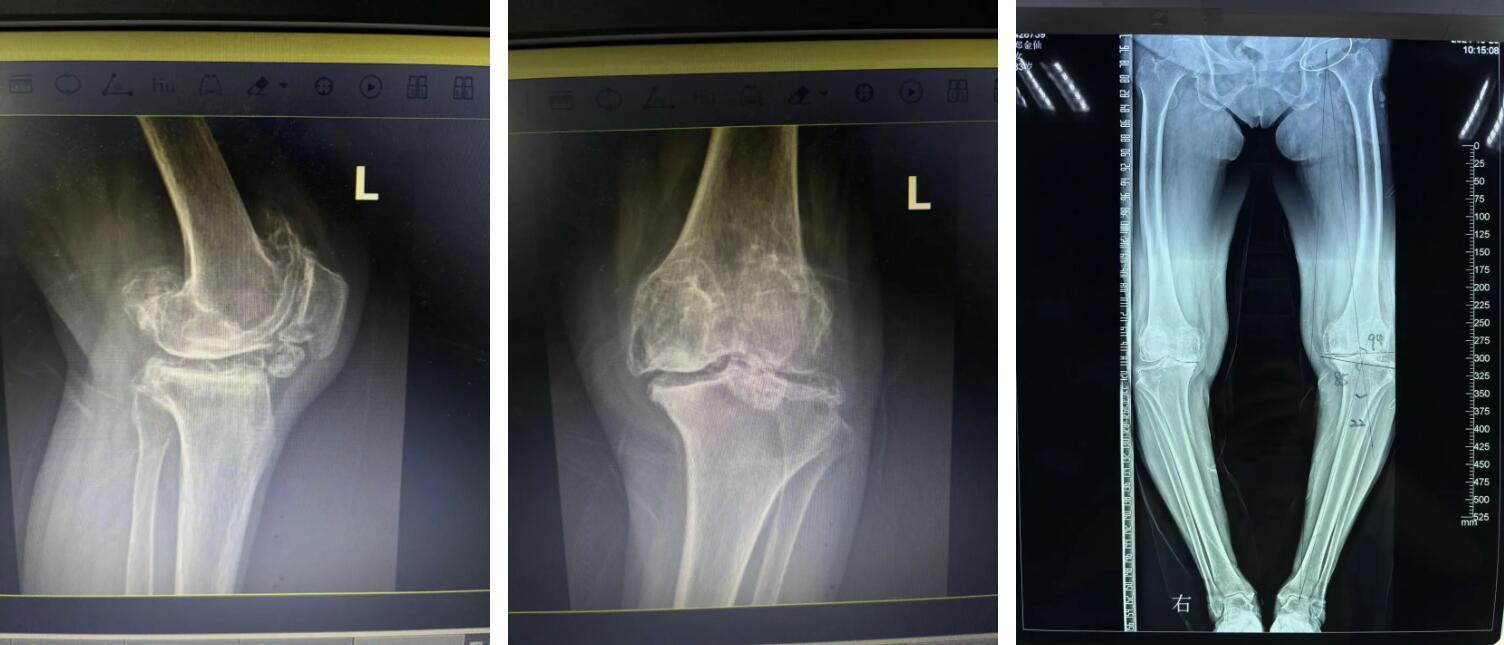

可是現(xiàn)如今阿婆雙膝部的疼痛逐漸加重,膝蓋也嚴(yán)重變形,終日苦不堪言,家里兒女看到后甚是心疼,最終經(jīng)過(guò)多方打聽(tīng)后,鄭阿婆在家人的陪同下來(lái)到廣安醫(yī)院找到了關(guān)節(jié)科羅軍副院長(zhǎng)。

羅院長(zhǎng)仔細(xì)了解鄭阿婆的病情后,第一時(shí)間為阿婆確定了左側(cè)人工全膝關(guān)節(jié)置換手術(shù)的治療方向,并制定了詳細(xì)的治療方案,最終得到了阿婆和家屬的一致認(rèn)同。

住院后,羅院長(zhǎng)立即給阿婆安排一對(duì)一術(shù)前規(guī)劃、術(shù)前3D打印,做到了關(guān)節(jié)置換的“量身定制”,最終在羅軍手術(shù)團(tuán)隊(duì)的努力下阿婆順利完成了機(jī)器人輔助下左側(cè)人工全膝關(guān)節(jié)置換手術(shù)治療。